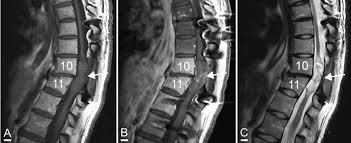

L’opération consiste à injecter des cellules souches de sa cavité nasale au niveau de la vertèbre accidenté. Avec ce processus, elle a pu retrouver sa mobilité d’antan grâce à la reconnexion des liaisons nerveuses entre elles. Cependant, huit ans plus tard, la jeune femme ressent des douleurs insupportables au niveau de son dos auquel s’ajoute un important gonflement avec des « secrétions de mucus »… Un nez était en train de se former dans son dos !

Une autre intervention d’un neurochirurgien à eu lieu afin d’extraire le nez qui poussait à l’arrière de son corps… Selon une chercheuse experte des « cellules souches », cet inconvénient inattendu n’arriverait que à 1 personne sur 100 ! Ce qui fait de cette américaine un cas rarissime…